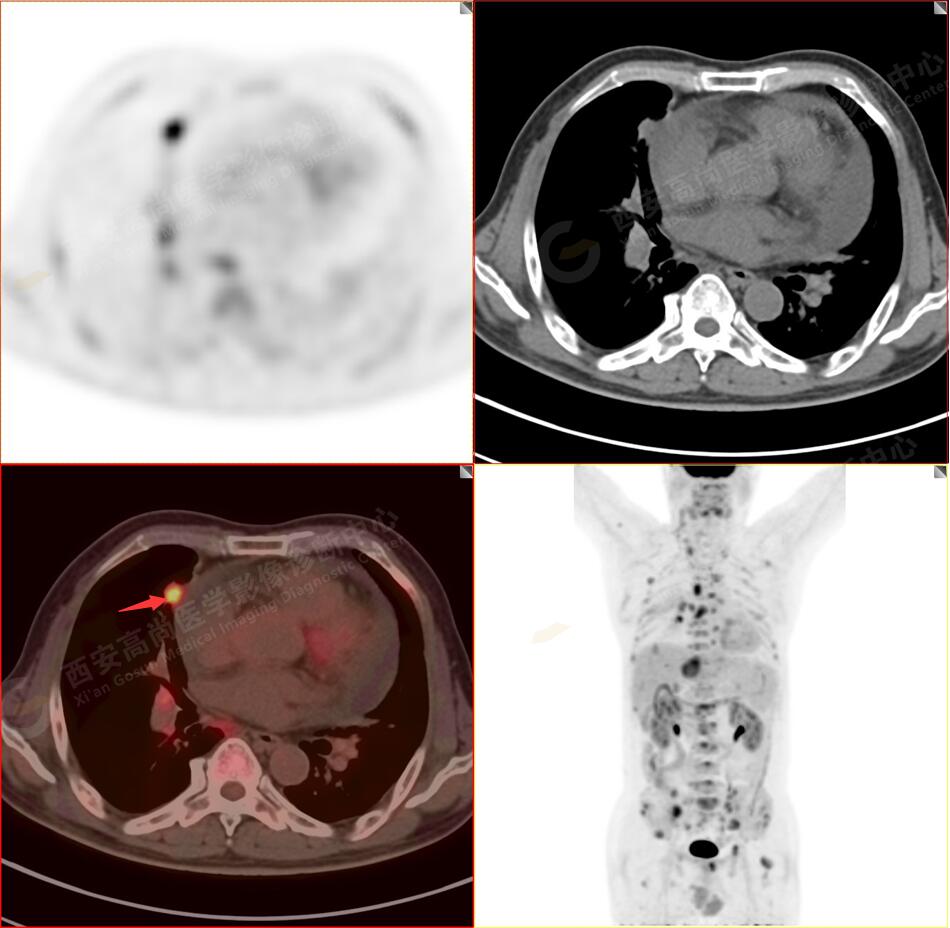

2.以下為全身多發(fā)轉移灶

2.雙肺內(nèi)彌漫性分布大小不等實性小結節(jié)灶及粟粒狀高密度影,均未見FDG代謝明顯異常增高,均多考慮為癌性淋巴結炎及轉移性病變。

3.右側頸部(Ⅱ-Ⅴ區(qū))、右側腋窩區(qū)、右側肺門及縱隔(1R、1L、2、4、6、7組)、肝門區(qū)多發(fā)腫大淋巴結,呈不同程度異常增高,均考慮為淋巴結轉移。

4.肝S4、8段團塊狀及結節(jié)狀低密度病變,以S4段病變?yōu)橹什煌潭菷DG代謝異常增高,考慮為肝多發(fā)轉移。

5.右側肱骨上段、左側肩胛骨、右側鎖骨胸骨端、胸骨、雙側多發(fā)肋骨、脊柱多發(fā)椎體及附件、雙側髂骨、雙側髖臼、雙側恥骨、雙側肱骨上段多發(fā)成骨性病變,呈不同程度FDG代謝異常增高,考慮為多發(fā)骨轉移瘤。